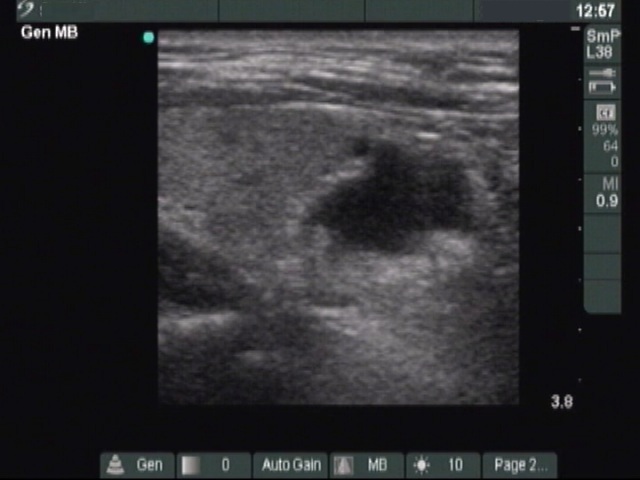

First session of therapy (ultrasonographic picture 3)

Left lobe, longitudinal scan. The parathyroid is located under the thyroid.